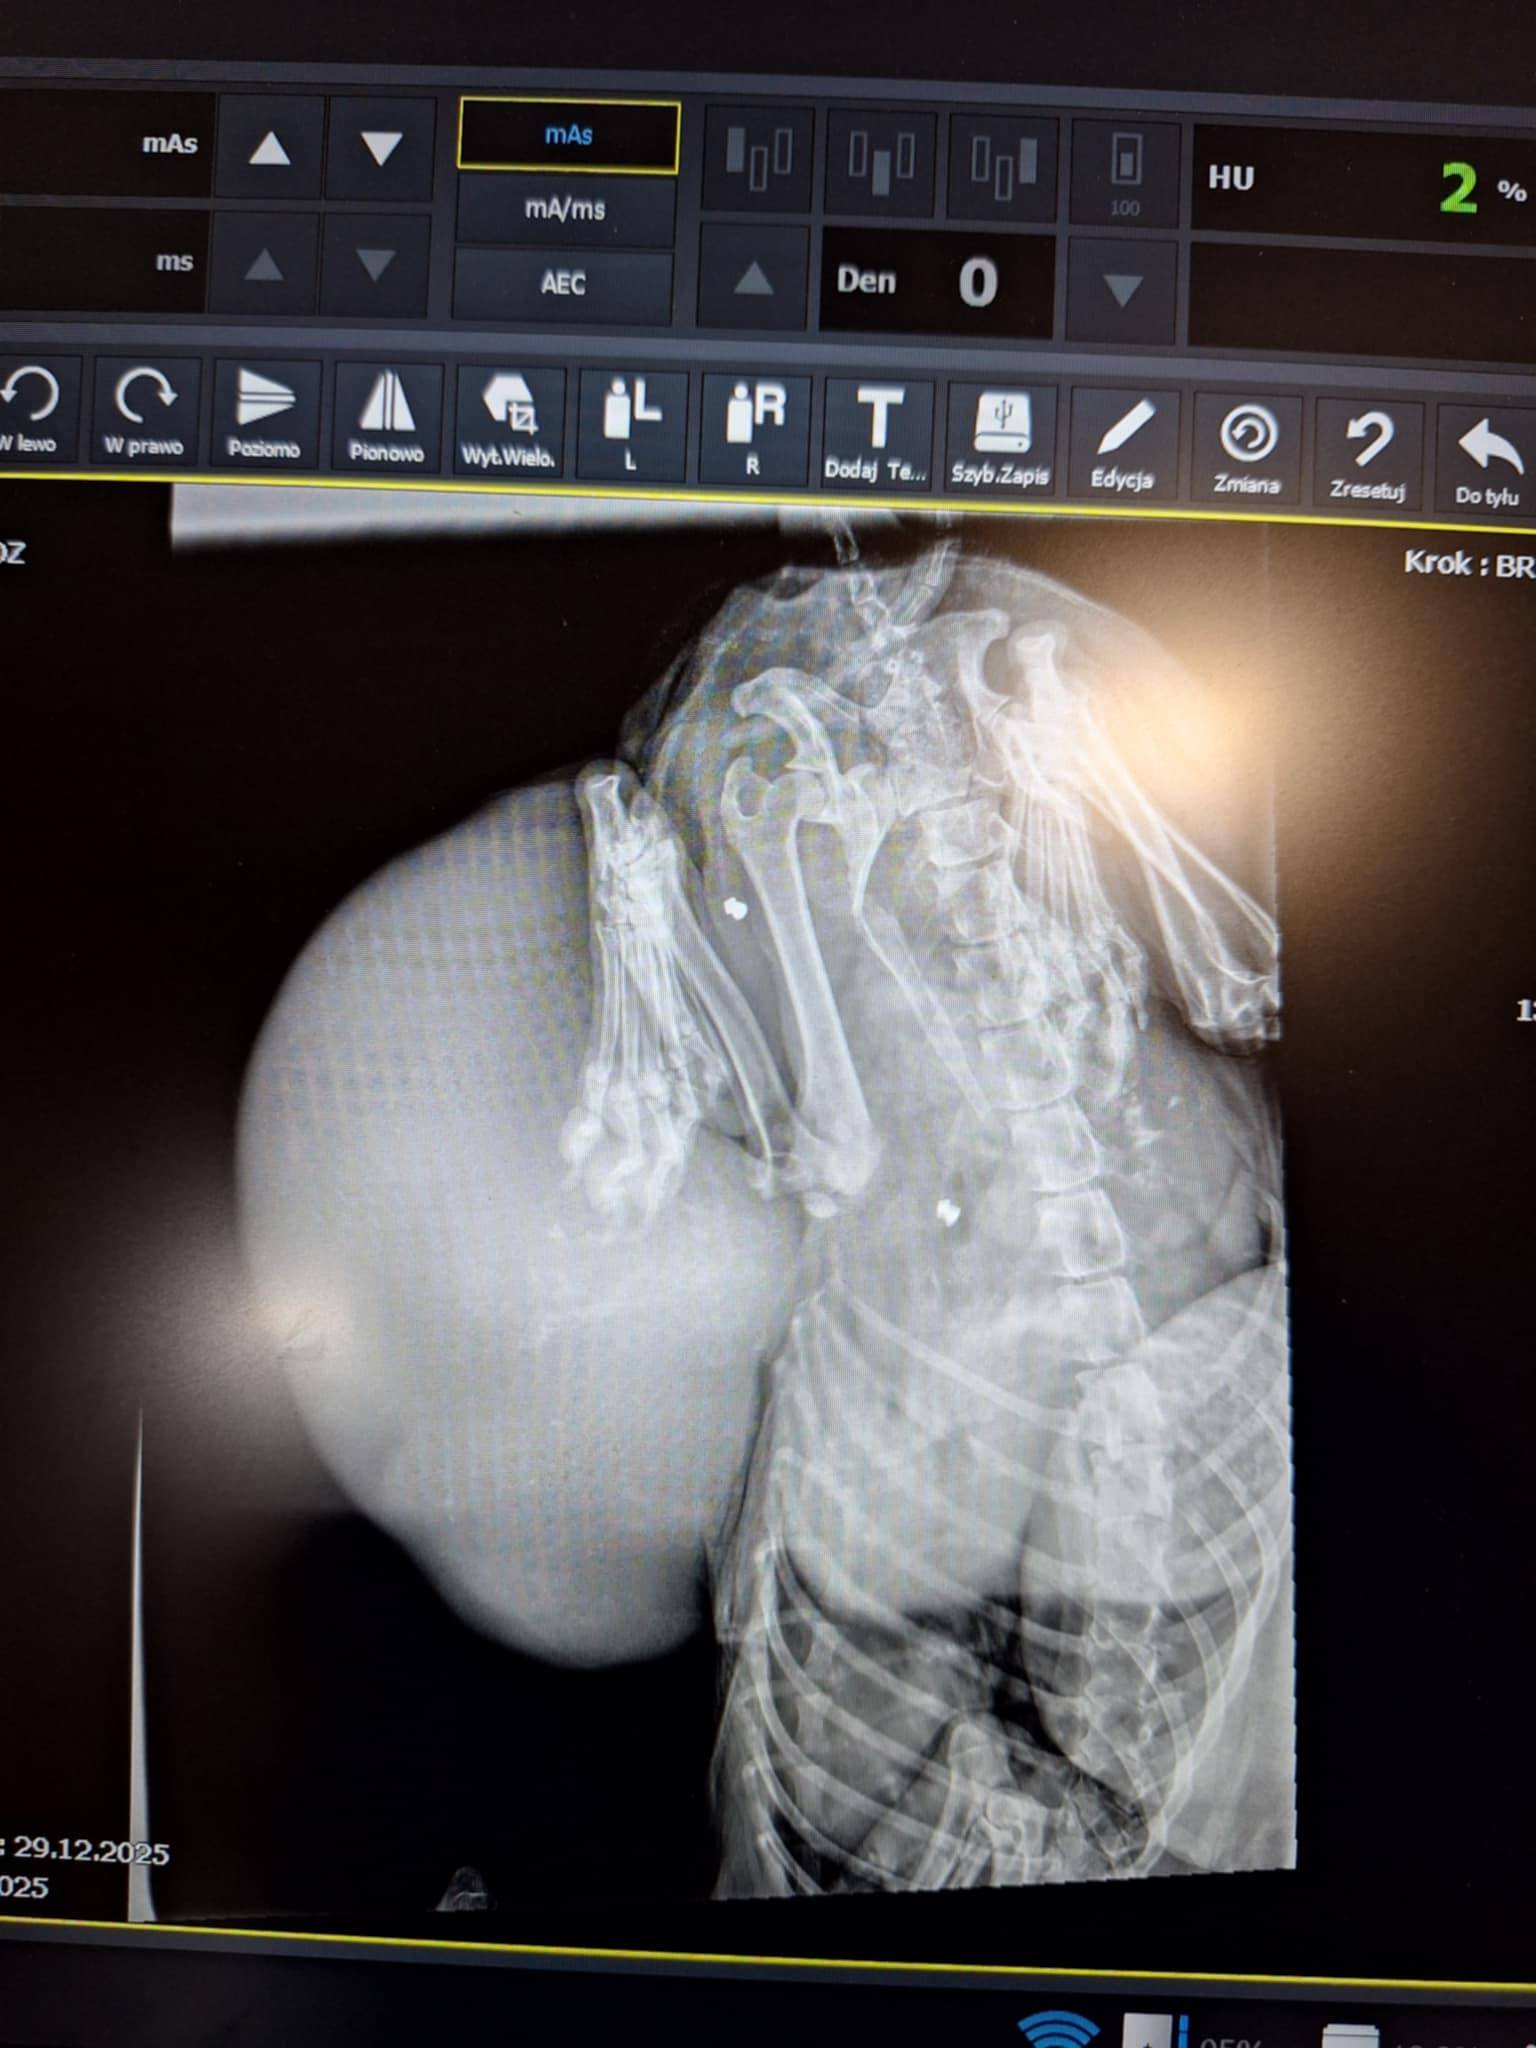

🐶 Pies z DWOMA OGROMNYMI GUZAMI NOWOTWOROWYMI. Jeden z nich był tak wielki, że ciągnął się po ziemi.

➡️ W organizmie liczne śruty – ślady po strzelaniu.

Do tego czasu pies musi zostać przygotowany – diagnostyka, badania krwi, USG, RTG, leczenie przeciwbólowe, odrobaczenie, odpchlenie, stabilizacja organizmu. 📢 To wszystko kosztuje. A my nie zostawimy go samego.